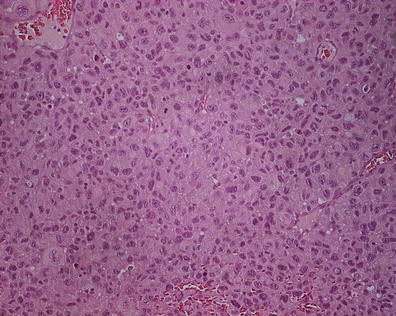

Objective: The aim of the study was to investigate Cellular Retinoic Acid Binding protein type I (CRABP I) expression and its clinical significance in pancreatic neuroendocrine tumors (pNETs).

Method: Protein expression of CRABP I was investigated by immunohistochemical analysis in 71 pNETs of various histological subtypes, including well- and poorly differentiated neuroendocrine neoplasms. Relationship of CRABP I expression to clinical and pathological features, grading and cell proliferation (index Ki-67) was analyzed.

Results: Increased expression of CRABP I protein was detected in 43.7 % (31of 71) of cases, including 16.7 % (1 of 6), 42.1 % (24 of 57) and 75.0 % (6 of 8) of pNET G1, pNET G2 and pNEC G3, respectively. We found the significant relationship of increased CRABP I expression to histological differentiation (p = 0.003), primary tumor size (p = 0.024), lymph node and liver metastases (p = 0.017 and p = 0.024, respectively) and cell proliferation, evaluated on the basis of the Ki-67(MIB-1) antigen expression (p = 0.000). The protein expression was not associated with outcome and survival of pNET patients.

Conclusion: The increased protein expression and association with high-risk factors suggest the great potential prognostic and therapeutic interest of evaluation of CRABP I in pNETs. Further study is necessary to clarify the role of CRABP I protein in pNET pathogenesis.

CRABP I expression in the cell cytoplasm of pNET G2 (Ki-67–9 %).: